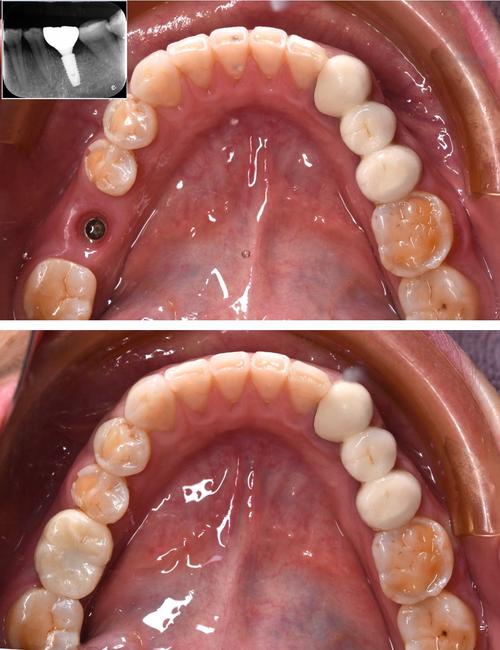

种植牙作为目前修复缺失牙的有效方式,其成功与否很大程度上取决于牙槽骨的条件,许多缺牙患者因长期缺牙、牙周病或外伤等原因,存在牙槽骨量不足的问题,此时便需要借助骨增量技术来为种植体创造稳定的“土壤”,在骨增量技术中,“种牙骨膜”是一个常被提及的关键概念,它究竟是什么?在种植牙中扮演什么角色?本文将详细解析。

- 即刻种植:在拔牙后即刻植入种植体,若拔牙窝骨壁不完整或骨量不足,可利用骨膜覆盖拔牙窝或种植体周围,促进拔牙窝的骨愈合和种植体周围骨整合。

- 术前评估:通过CBCT、口腔曲面断层片等影像学检查评估骨缺损情况,设计手术方案,确定骨膜来源和取骨区(若使用自体骨膜)。

- 复诊:按时复诊,通过影像学检查评估骨再生情况,通常术后3-6个月待骨成熟后再进行种植体植入。